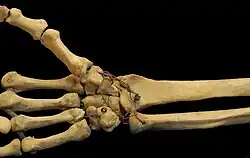

Ligaments

These four CMC joints are supported by strong transverse and weaker longitudinal ligaments: the dorsal carpometacarpal ligaments and the volar or palmar carpometacarpal ligaments.[7]

The interosseous ligaments consist of short, thick fibers, and are limited to one part of the carpometacarpal articulation; they connect the contiguous inferior angles of the capitate and hamate with the adjacent surfaces of the third and fourth metacarpal bones.